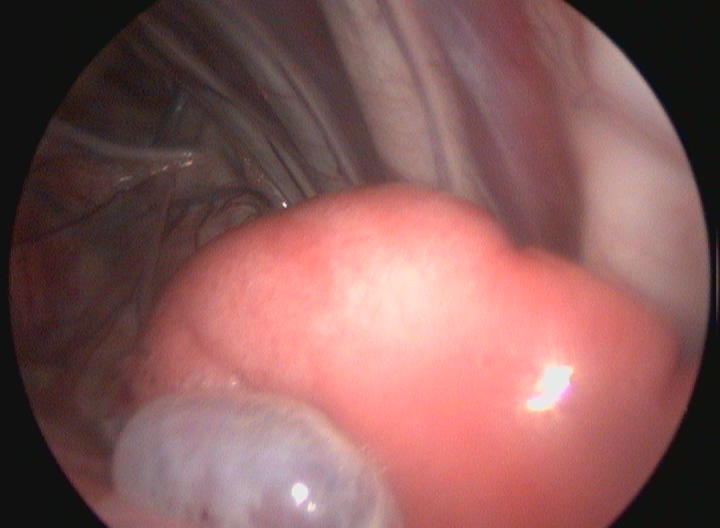

L'Endoscopia è una branca della diagnostica per immagini che permette di ottenere immagini fotografiche e filmati attraverso l'utilizzo di piccole telecamere.

L'Ospedale degli animali è in grado di eseguire esami endoscopici, quali gastroduodenoscopia, colonscopia (con prelievi bioptici) ed endoscopia delle vie respiratorie comprensive di BAL, brushing (per la citologia diagnostica ) e biopsia. La videondoscopia è una tecnica rapida e sicura e che spesso si coniuga con la chirurgia delle vie respiratorie.